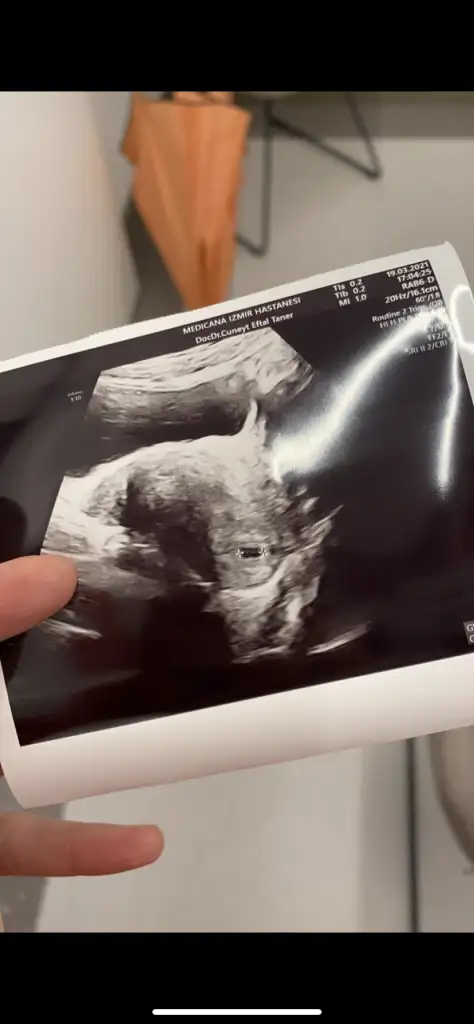

dr soylemeden siz gorun genital nub teorisi ( bebegin cinsiyeti)

Kız görünüyor

Canim yeni fotolarim geldi bakabilir misin bir Dr erkek dedi Kordon'da olabilir dedi..bugünde başka Dr gittim kıza benziyor dedi..kalp atışı olan fotoda solda bacakları nubu var yandan da baktı dr görebilmek için .sen ne düşünüyorsun

Emin olmadım ama kız sanki önceki usgde kız demiştim